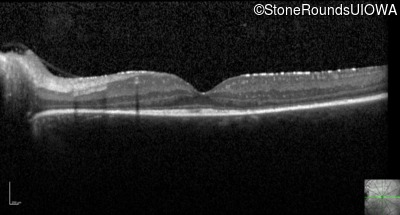

Optical Coherence Tomography - Right - 20/30 -1

Exemplar / OCT Stack